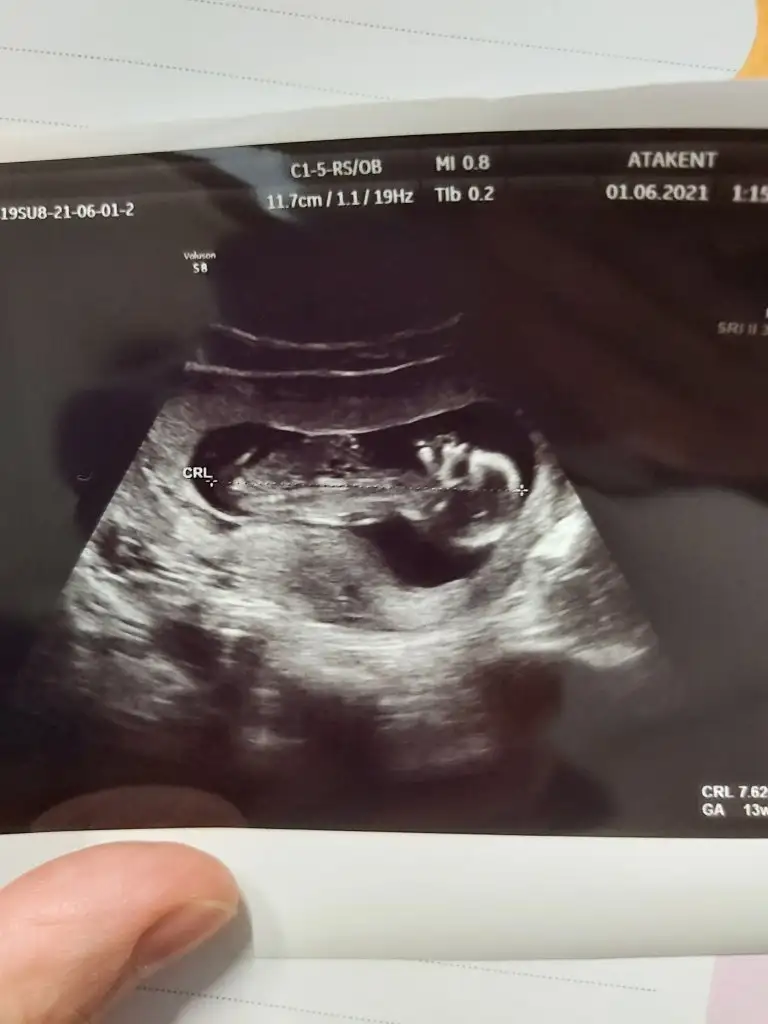

Ultrason fotoğrafında burun kemiği

Al bacım 14. Hafta hem daha küçük

İkili tarama yaptı temiz geldi dedi ne ensesi şu kadar ne burun kemiği bu kadar demedi sadece üçlü yerine dörtlü yaptı onda da 1:869 çıkmış orta risk down sendromu var dedi ama ultrasonda hiç ensesi kalın falan demedi downlu bebekler galiba minik olurmuş bana tam tersi dörtlünün sonucunu söylediği gün ultrasonda bunun bacağı uzun ha uzun boylu olur dedi

Bu test kağıdında ense kalınlığı , burun kemiği yazar zaten

Sadece burna degil ense kalınlığında falan da bakılıyor onla ilgili bir sey demedi mi